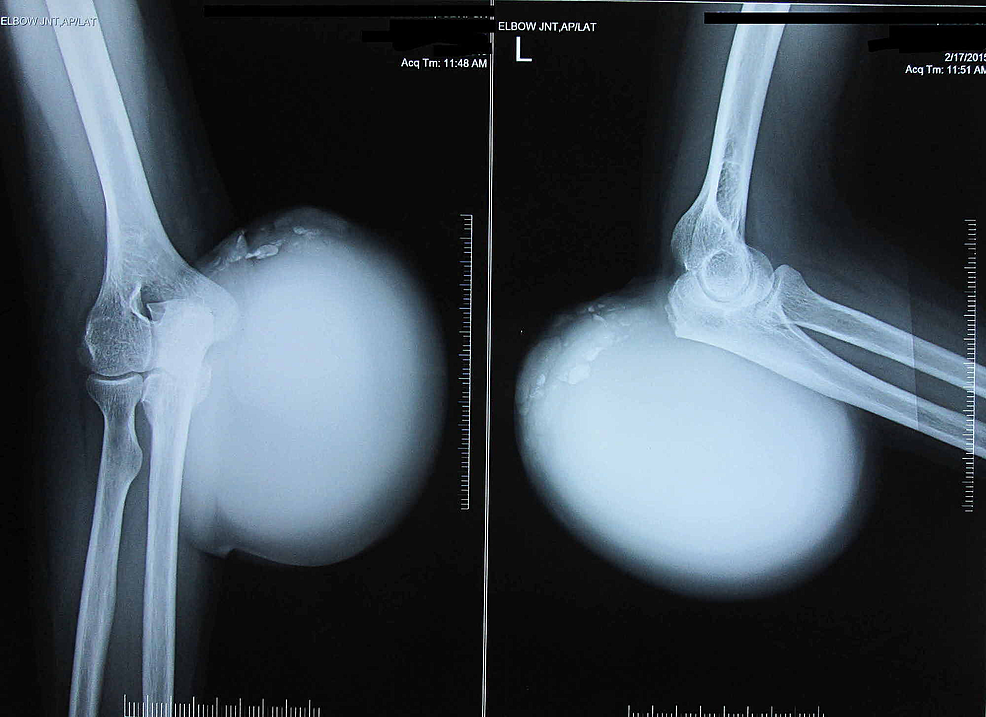

From www.cureus.com

Cureus Massive Gouty Tophi Presenting as Pseudotumor of the Elbow A Can Gout Be In Elbows Gout in the elbow joint, also known as gouty arthritis, can cause symptoms such as severe pain, swelling, redness, and limited range of. Elbow gout or gout in elbow can cause swelling, redness, and pain to occur in that region of the body. Gout usually affects the big toe, but it can occur in any joint. The simple answer is. Can Gout Be In Elbows.